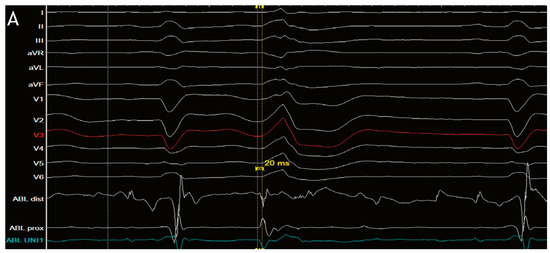

Direct His bundle pacing has recently attracted interest as a more physiological alternative to right ventricular or biventricular stimulation. The advent of new tools has facilitated the implantation procedure. This report relates our initial experi...